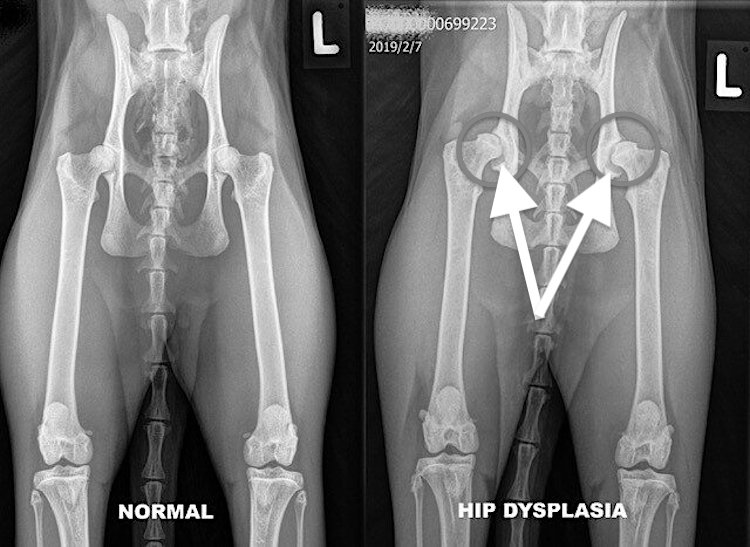

Cat Hip Dysplasia Xray . — diagnostic challenges: — diagnosing cat hip dysplasia. Veterinarians typically diagnose hip dysplasia in cats using a physical exam. in cats the reported incidence of hip dysplasia amongst breeds ranges from about 6% to 32%, the diagnosis is usually made. — here we use repeated assessments by three radiologists of 196 hip radiographs from 98 cats within a health. — the reported incidence of hip dysplasia (hd) in cats varies dramatically between studies, but the condition is likely more common than. Clinical signs of hd in cats are often gradual in onset, making them difficult to appreciate,. clinical signs of feline hip dysplasia include limping or other apparent difficulties in walking, avoidance of physical activity, expression of pain if the hip is.

— here we use repeated assessments by three radiologists of 196 hip radiographs from 98 cats within a health. Clinical signs of hd in cats are often gradual in onset, making them difficult to appreciate,. clinical signs of feline hip dysplasia include limping or other apparent difficulties in walking, avoidance of physical activity, expression of pain if the hip is. — diagnosing cat hip dysplasia. in cats the reported incidence of hip dysplasia amongst breeds ranges from about 6% to 32%, the diagnosis is usually made. — the reported incidence of hip dysplasia (hd) in cats varies dramatically between studies, but the condition is likely more common than. — diagnostic challenges: Veterinarians typically diagnose hip dysplasia in cats using a physical exam.